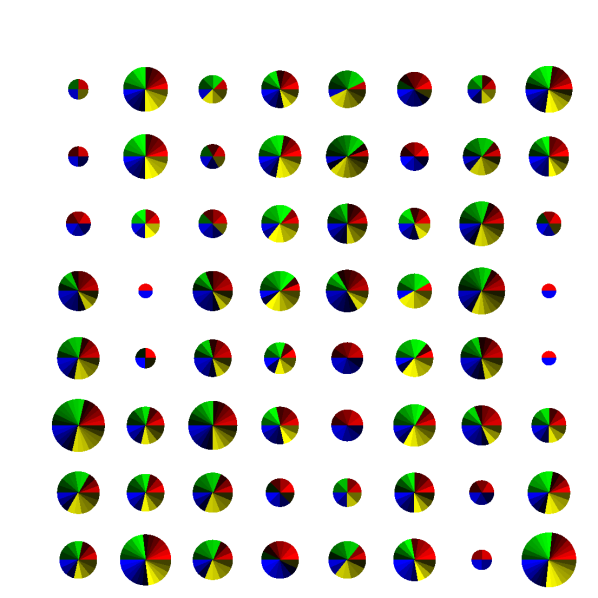

Figure 1 shows a 8×8888\times 8 patch of k-space generated by the patterns with acceleration factor 𝑹=[2,3]𝑹23\bm{R}=[2,3] and Q=72𝑄72Q=72. In this visualisation, each pie slice corresponds to one readout and has a constant area. Hence, the area of each pie corresponds to the number of times with which that k-space position is sampled in the entire acquisition.

Refer to caption

(a) Regular

(b) Treg

(c) Sreg

(d) TSreg

(e) Random

(f) Halton

(g) Legend

Fig. 1: Graphical representation of undersampling patterns for 𝑹=[2,3]𝑹23\bm{R}=[2,3], k-space size of 8×8888\times 8 and number of contrasts Q=72𝑄72Q=72. Legend: each row represents a set of contrasts, grouped together with according to contrast property such as inversion times.